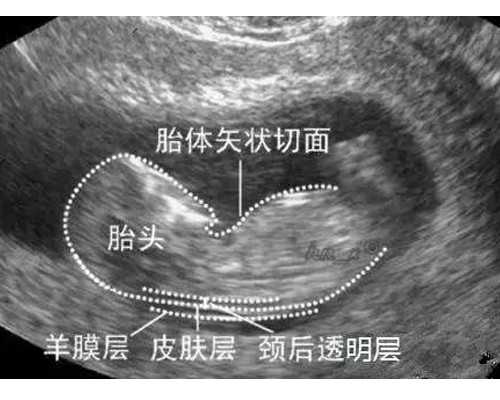

月经第2-3天b超基础卵泡监测:检查子宫和卵巢,统计大小卵泡数量。

月经第12天,阴道b超检查:子宫环境子宫内膜厚度(大小是否正常,是否有肌瘤、息肉等。)(8-12mm有利于胚胎着床)。